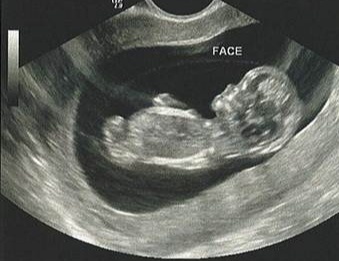

Гематома при беременности 12 недель

Девочки, скрининг в 12 недель напугали наличием гематомы. На следующий же день побежала в платную клинику к своему Г. Она посмотрела, подтвердила... Выписала кучу препаратов, постельный режим, половой покой и т.д.

По истечению срока, пошла на контрольное УЗИ, которое показало наличие гематомы уже в разы меньше, но она всё ещё присутствует. Врач посоветовала мне сменить Ж. К.